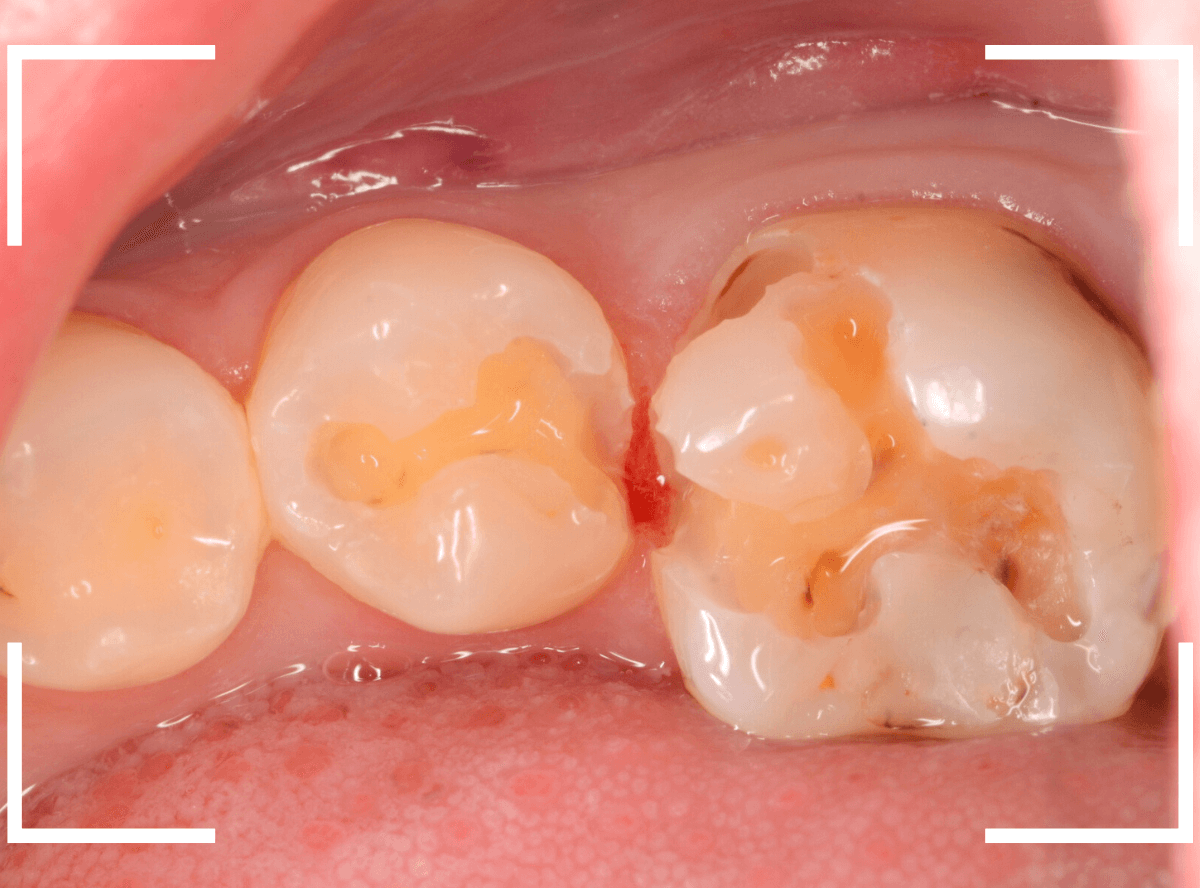

Case.8 大きな虫歯なのに、レントゲンではっきり写らない

こちらも定期検診希望で来院された患者さんです。

お口の中を拝見すると、明らかに虫歯がありました。

3本虫歯になっており、特に中央の小臼歯はかなり大きな虫歯になっているのが予想されます。

治療前にレントゲン写真で虫歯の大きさを確認するつもりが・・・あまりはっきり写ってきません。

患者さんに状況を説明して、歯を少しずつ削りながら虫歯を確認する事になりました。

まず、一番大きな虫歯と思われる部分を小さく削って確認します。

予想通り、虫歯が見えてきました。

隣りの奥歯と一緒に虫歯の治療を進めます。

色が染まっているところがまだ虫歯が残っている部分です。

2本とも、虫歯を全て取り切りました。

特に手前の歯はかなり広めの虫歯になっていました。

最終的に、手前の虫歯の除去も終わったところです。

手前の歯の虫歯は中央の歯まで達していました。

このように明らかに大きな虫歯があると診断されるような状況でも、レントゲン写真でうまく診断できない場合もあります。